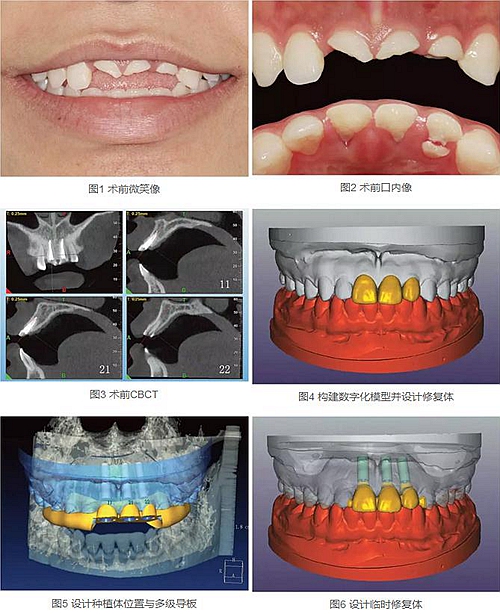

23歲女性患者,外傷導(dǎo)致上前牙折斷3天。檢查:中微笑線;上頜右側(cè)中切牙至左側(cè)側(cè)切牙殘根,不松動,腭側(cè)缺損達(dá)齦下5mm,牙齦中等厚度,齦緣基本完好。CBCT顯示:根長約11mm,牙根長軸與牙槽突方向基本一致,唇側(cè)骨板完好、厚度1.0mm,可用骨高度21mm。全身情況良好。

拍攝臨床照片、拍攝輕開口位CBCT(NewTom)、取聚醚印模灌制超硬石膏模型。

構(gòu)建數(shù)字化模型并設(shè)計修復(fù)體:將超硬石膏模型在口外掃描(Identica Hybrid),獲取軟硬組織表面形態(tài),構(gòu)建數(shù)字化模型,確認(rèn)咬合情況。根據(jù)天然牙殘根頸部形態(tài)設(shè)計修復(fù)體頸部形態(tài),使修復(fù)體頸緣輪廓與原有天然牙一致;按正常牙弓弧度與覆、覆蓋關(guān)系,結(jié)合紅白美學(xué)等原則確定修復(fù)體的三維形態(tài)。最后,導(dǎo)入患者面部照片,確認(rèn)模擬修復(fù)效果。

設(shè)計種植體位置并制作多級導(dǎo)板:利用Segma設(shè)計軟件,將CBCT數(shù)據(jù)和模型掃描數(shù)據(jù)進(jìn)行配準(zhǔn),調(diào)入模擬修復(fù)效果數(shù)據(jù),以修復(fù)為導(dǎo)向設(shè)計種植方案,設(shè)計種植體螺絲孔開口從修復(fù)體舌窩處穿出,最終實現(xiàn)螺絲固位的一體化基臺冠修復(fù)。根據(jù)種植體信息設(shè)計多級導(dǎo)板,參考修復(fù)體形態(tài)設(shè)計導(dǎo)板植入?yún)^(qū)頸緣外形,打印生成種植導(dǎo)板(Segma),并安裝金屬引導(dǎo)環(huán)。

設(shè)計并制作臨時修復(fù)體:如前所述,按照美學(xué)效果和咬合關(guān)系設(shè)計臨時冠外形,頸部形態(tài)與模型齦緣輪廓一致,保證臨時修復(fù)體在術(shù)后可以封閉拔牙窩。3顆臨時冠為連冠,齦外展隙適當(dāng)加大,為術(shù)后軟組織生長提供一定的空間。在臨時冠近兩側(cè)鄰牙的切角處預(yù)留翼板,保證臨時冠戴入時可以找到準(zhǔn)確的位置。以銑削的方式加工臨時冠(Segma),待種植體植入后將其在口內(nèi)粘接于臨時基臺上。

術(shù)中不翻瓣微創(chuàng)拔除牙根,牙槽窩骨壁完整。在多級導(dǎo)板輔助下完成種植窩洞制備,植入Bego柱形種植體,型號分別為:上頜右側(cè)中切牙位點4.1mm×15mm、上頜左側(cè)中切牙位點 3.75mm×15mm、上頜左側(cè)側(cè)切牙位點3.25mm×15mm,扭矩均為35N·cm。種植體與唇側(cè)骨壁間隙約2mm,植入骨膠原(注:Geistlich Bio-Oss®Collagen 膠原骨)。戴入橋用鈦臨時基臺,臨時冠就位順利,自凝樹脂口內(nèi)粘接后適當(dāng)修整外形,充分磨光,調(diào)至正中、前伸和側(cè)方與對頜牙均無接觸。術(shù)后根尖片顯示種植體位置、方向良好。